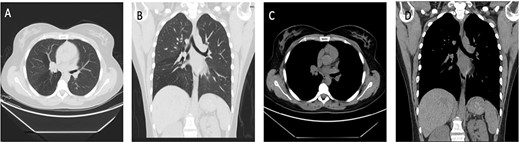

A 34-year-old female, who is a known case of ulcerative colitis, has been followed by a pulmonologist due to a chronic cough, that was first treated as asthma; but did not resolve with the management plan set by the pulmonology service. A CT scan (Fig. 1) was then conducted on this patient that showed right endobronchial lesion. Afterwards, this patient underwent bronchoscopy and a biopsy was taken from the cherry-like lesion mentioned. Pathology confirmed the diagnosis to be a typical carcinoid tumor (Fig. 1; case 1). The decision was made by the treating team to take the patient for tissue-sparing endobronchial resection. During the operation, the lesion was identified in the right intermedius bronchus, and by the use of a bronchoscopic snare and electrocautery, it was separated and removed en bloc.

Case 1: (A and B) Lung window showing endo-bronchial lesion at the right bronchus intermedius with air trapping middle and lower lobes. (C and D) Same lesion evident on mediastinal window on both axial and coronal cuts.